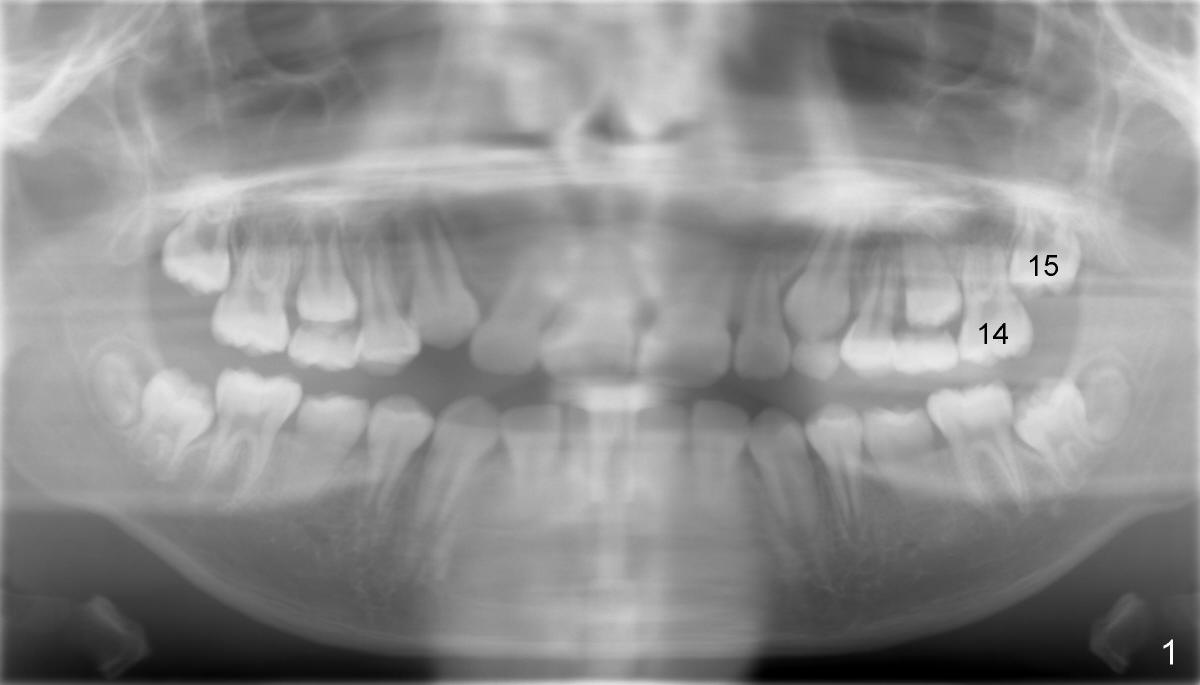

An eleven-year-old Chinese boy presented to my office for new patient exam in 2009.  Panoramic X-ray shows crowded dentition (Fig.1).  Orthodontic treatment was finished by a specialist in 2012.  Post-op X-ray shows that the tooth #15 (upper left 2nd molar) is impacted (Fig.2).  Fig.3 and 4 are magnification of Fig.1 and 2, respectively, demonstrating the change in the axis of #15 from 2009 to 2012 (red line).